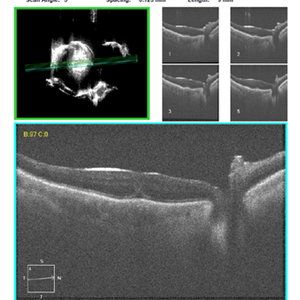

-

AVM 2

Jun 29 2014 by John S. King, MD

Atrophy of lesion with observation.

Photographer: Wayne A Ladlee Jr

Imaging device: Cirrus

Condition/keywords: aquired vitelliform maculopathy